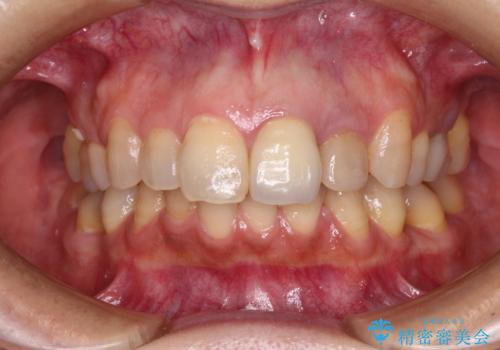

真ん中のオールセラミッククラウンを正面から見ると大変自然に仕上がっているのですが、側方から見ると白色が強く、さらには隣の歯は神経が除去されて変色していたため、コントラストでより色の違いが際立っていました。

前歯2本をオールセラミッククラウンにて補綴治療することとしました。